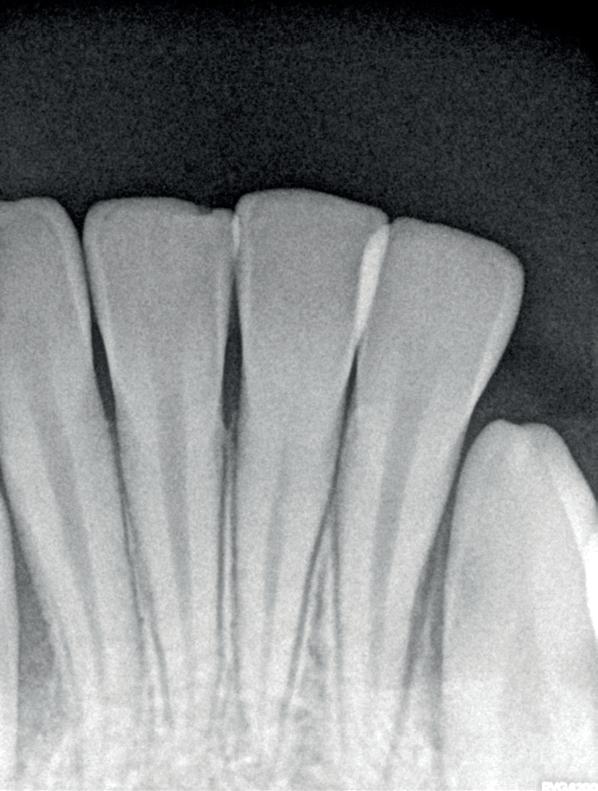

Voordat je aan een wortelkanaalbehandeling begint, zorg je voor (of maak je) een goede beginfoto waar het te behandelen gebitselement volledig op staat afgebeeld. Deze foto geeft essentiële informatie: de grootte van de pulpakamer en de ligging ervan; het aantal en de vorm van de wortels en de breedte van hun wortelkanalen en de lengte van de wortels. Hiermee kan je de DETI-score bepalen en de moeilijkheidsgraad inschatten. De grootte en de ligging van de pulpakamer op de röntgenfoto in combinatie met de ideale anatomische vorm, zoals in foto 1 is aangegeven, bepaalt de uiteindelijke vormgeving van de opening. Bij de molaren liggen de kanaalingangen in de buurt van de knobbeltoppen. Als die niet meer in originele staat

(kroon, restauratie) zijn, kan je ook de wortel gebruiken. Soms moet je net subgingivaal sonderen, maar de kanaalingang ligt in het middel van de wortel. Als je die plek visualiseert en projecteert op je opening, boor je de goede kant op. Nog een tip: wees bij het openen niet spaarzaam met het wegnemen van aanwezig restauratiemateriaal (wees wél spaarzaam met het onnodig wegnemen van tandweefsel).

1. De locatie van de kanaalingangen ten opzichte van de occlusale morfologie (rood). In zwart is de ideale of standaard opening ingetekend. De uiteindelijke vorm van de opening is voorts ook afhankelijk van de klinische situatie, die vooral vanuit een goede begin foto wordt verkregen.